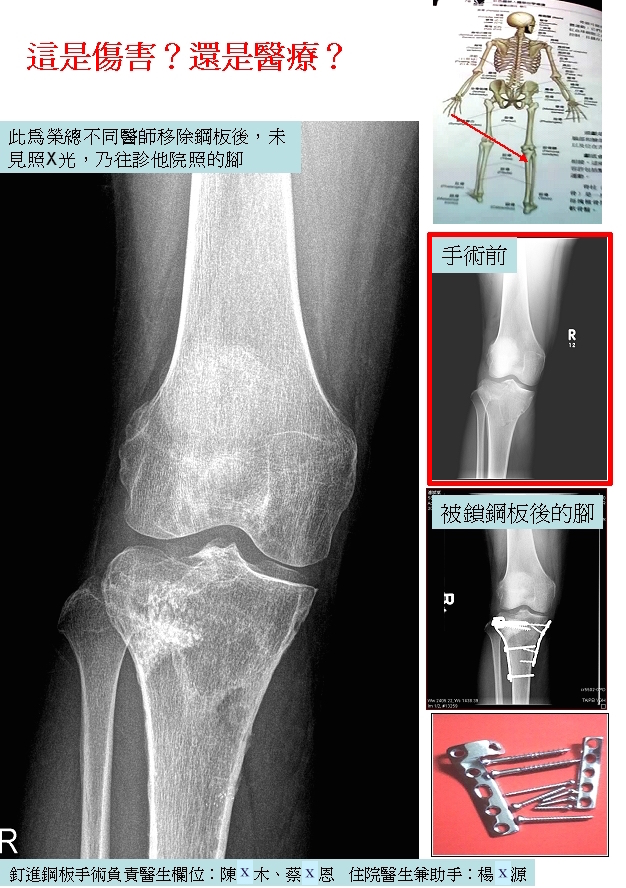

民眾提供之骨科糾紛案例01